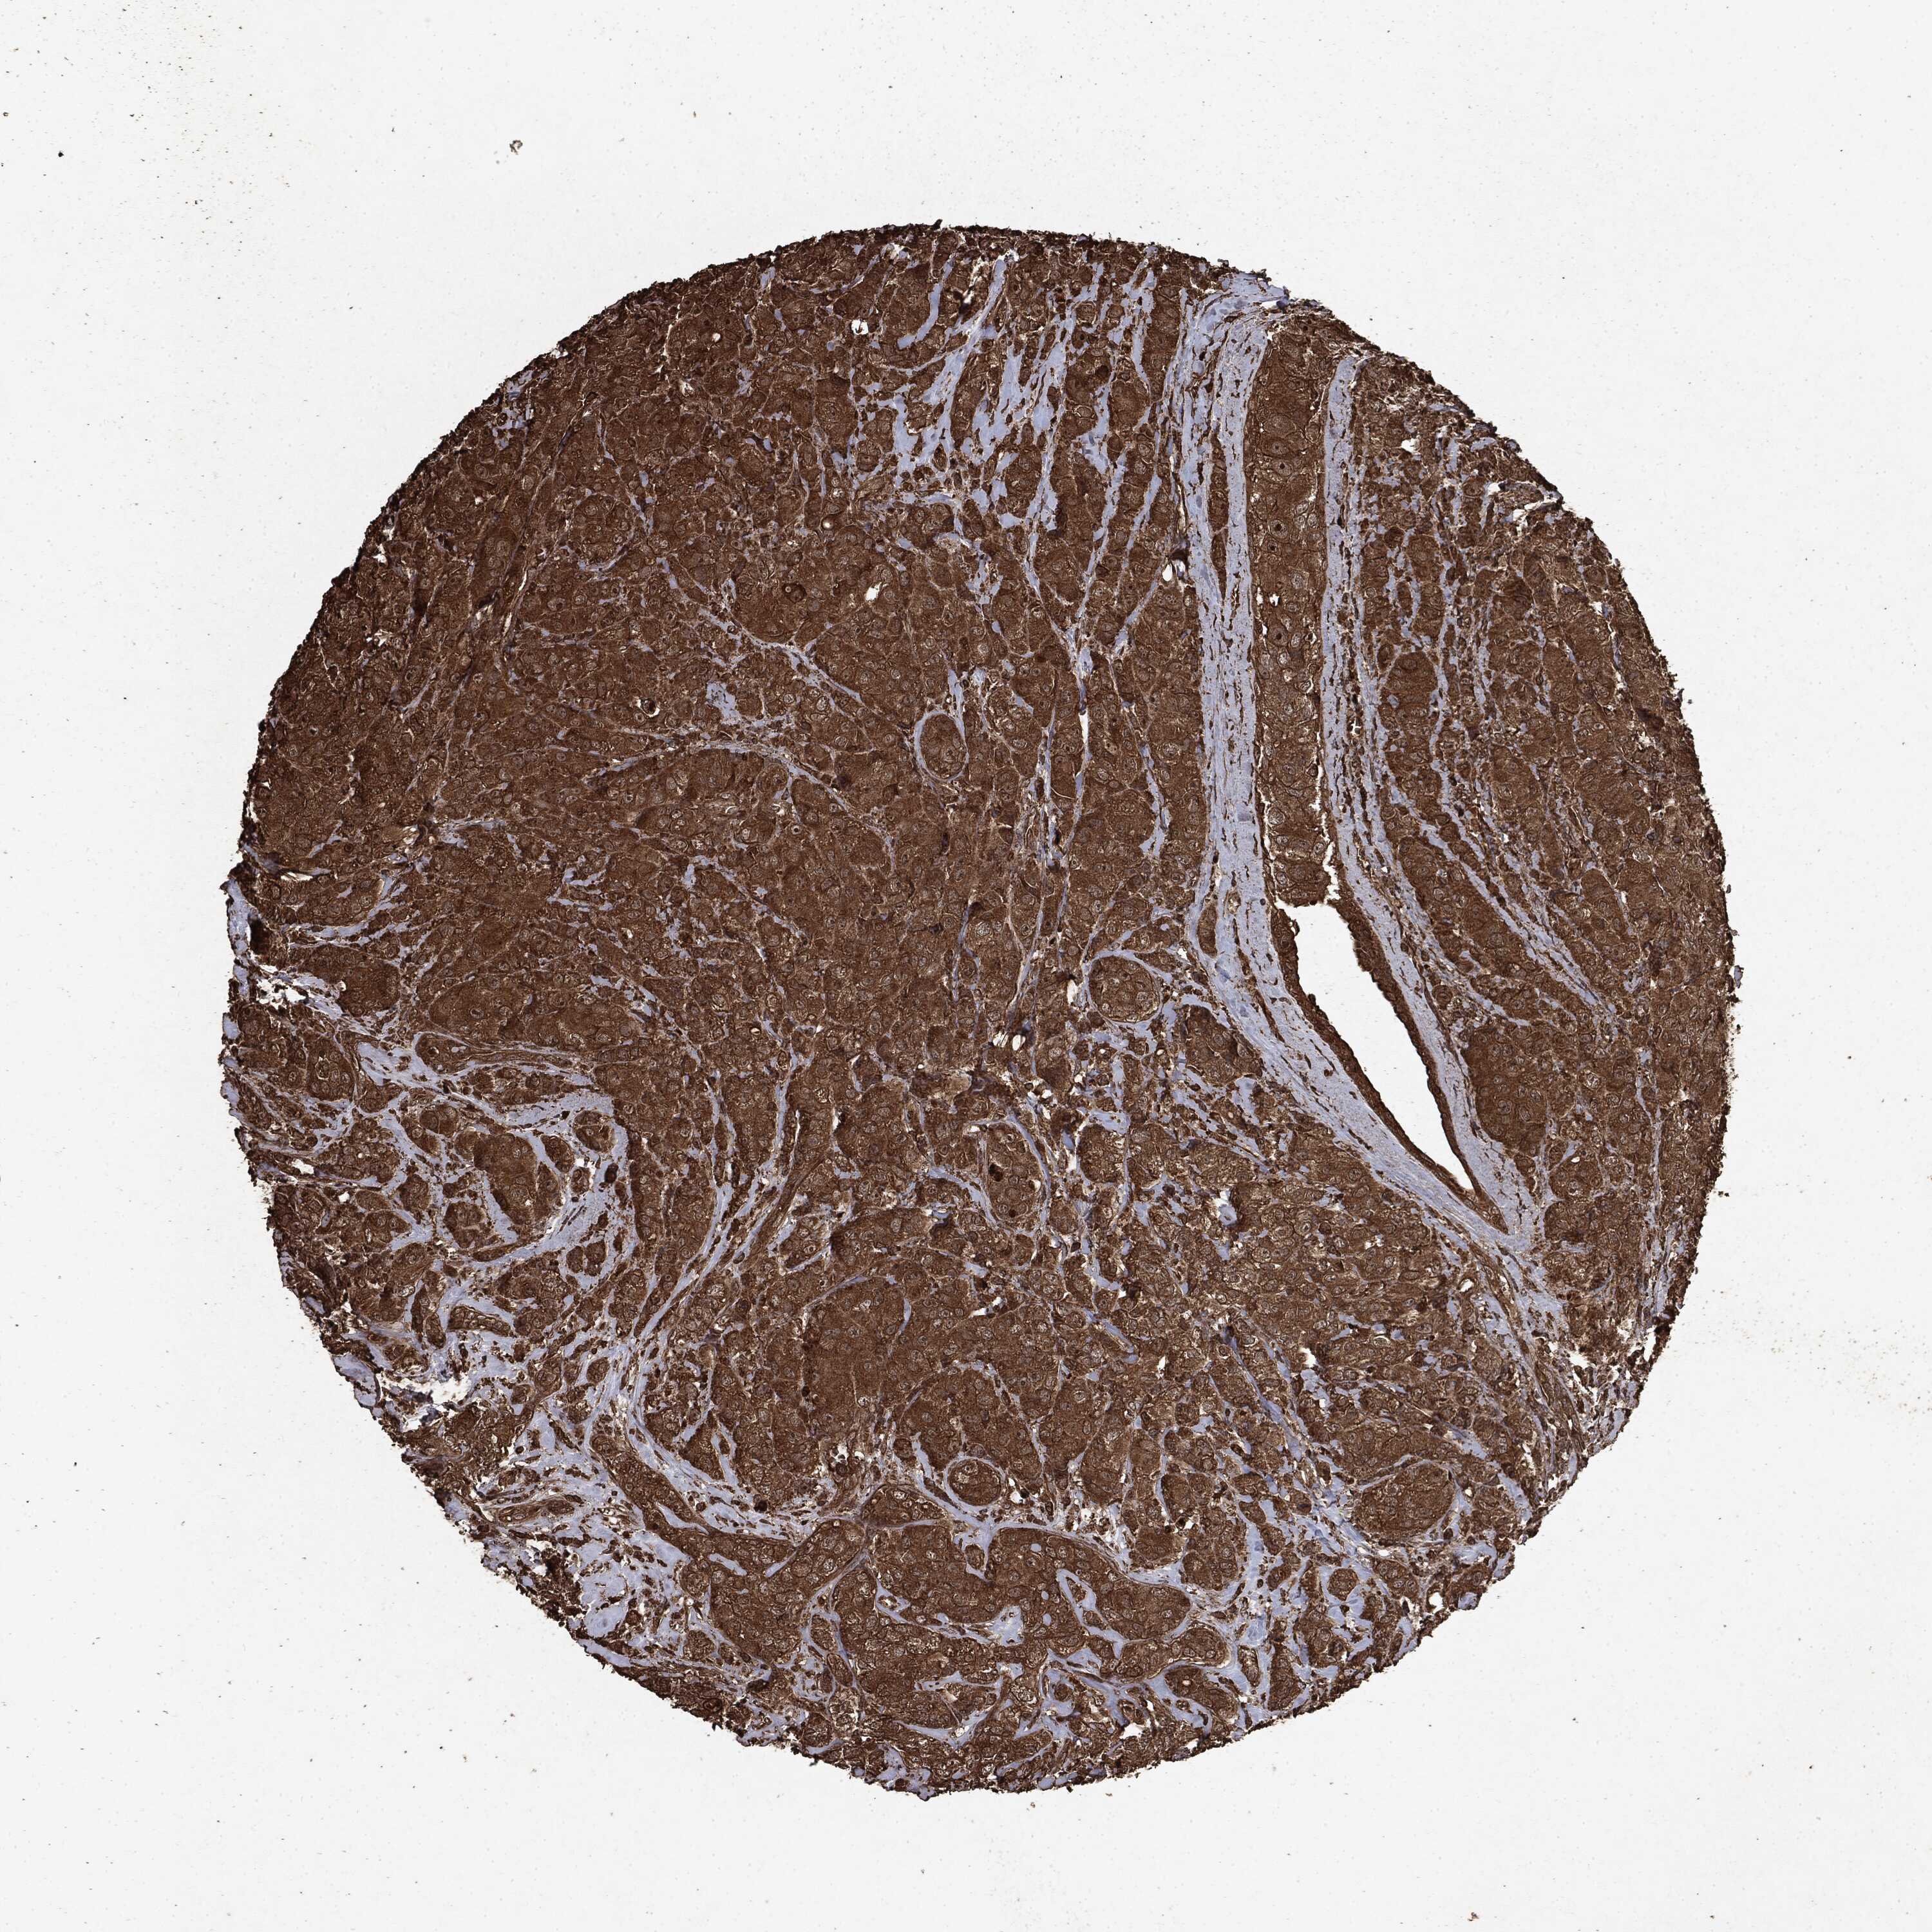

BRCA TCGA BRCA VALIDATION PROTEIN EXPRESSION

ANTIBODIES

AND

VALIDATION